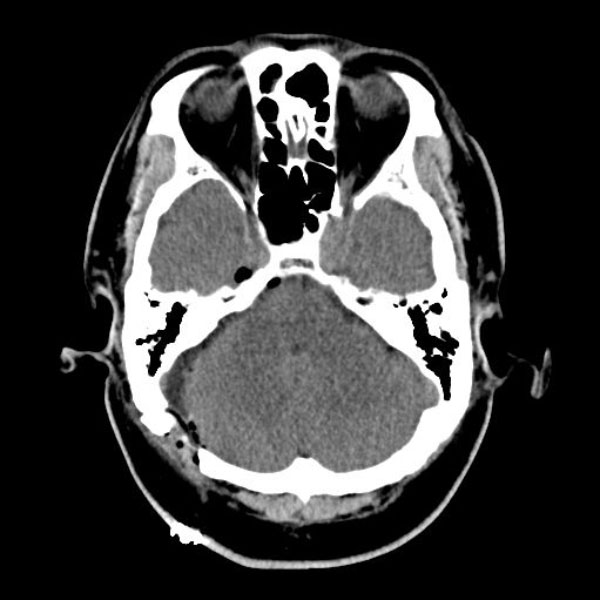

症例 '26年3月

No.

584

'26年3月

50代

三叉神経痛第3枝領域

手術前